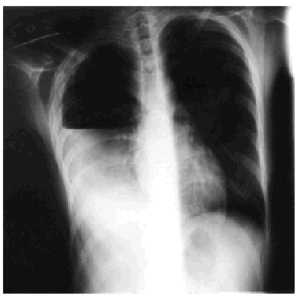

Treatment with rifampicin, isoniazid, and pyrazinamide was commenced upon admission, and sensitivity to all of them was later confirmed. Forty-eight hours after admission, the patient's cough suddenly worsened and increased shortness of breath developed with intense pleuritic pain on the right side. Radiological examination revealed a subtotal pneumothorax of the right lung. A drainage tube was inserted and a yellowish, translucent fluid was removed and found to contain 17.20 leukocytes (80% segmented, 12% with polymorphic nuclei, 0% eosinophils, 8% lymphocytes, and 0% monocytes), and a red blood cell count of 0.01x106/µL. Blood tests revealed pH to be 7.19, glucose 56 mg/dL, total proteins 4.1 g/dL, cholesterol 48 mg/dL, lactate dehydrogenase 9573 U/L, amylase 47 U/L, and adenosine deaminase 82 U/L. A culture of the pleural fluid was positive for M tuberculosis. The chest pain remitted, the pneumothorax resolved, and the drainage tube was removed after 15 days. Fever occasionally as high as 39.5 ºC persisted. Forty-eight hours later the chest pain reappeared and coughing became more frequent, with no increase in expectoration. The x-ray showed a recurrence of pneumothorax, pleural effusion, and right pleural thickening (Figure). A thoracic drainage tube was inserted again and a thick, purulent fluid was removed. Tuberculous aggregates were identified in the Ziehl stain and no concurrent infections were found. A computed tomography (CT) scan of the thorax confirmed the pneumothorax, the loculated pleural effusion, and the pleural thickening. Because of the pleural thickening, the persistence of fever and of empyema, thoracic surgery was considered necessary. A pleural decortication was performed. Visceral and parietal pleural thickening, a posterior empyematic chamber, and a cavity in segment 6 open to the pleural space were detected during the procedure. A few days later the patient was asymptomatic with mild residual pleural thickening and was negative for M tuberculosis within a few weeks.

Figure. Thoracic x-ray: pleural empyema.